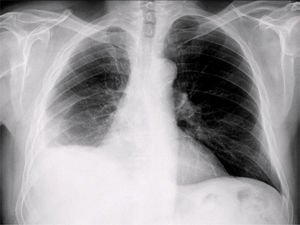

Presentamos el caso de un paciente de 63 años que consulta por disnea desde hace 15 días que se ha convertido a medianos esfuerzos desde hace unos meses. Exfumador de 10-15 cigarros al día hasta hace 20 años. Exposición laboral al amianto. Se efectúa radiografía de tórax urgente desde atención primaria con el siguiente resultado:

- •Radiografía de tórax anteroposterior (fig. 1): disminución de volumen del pulmón derecho.